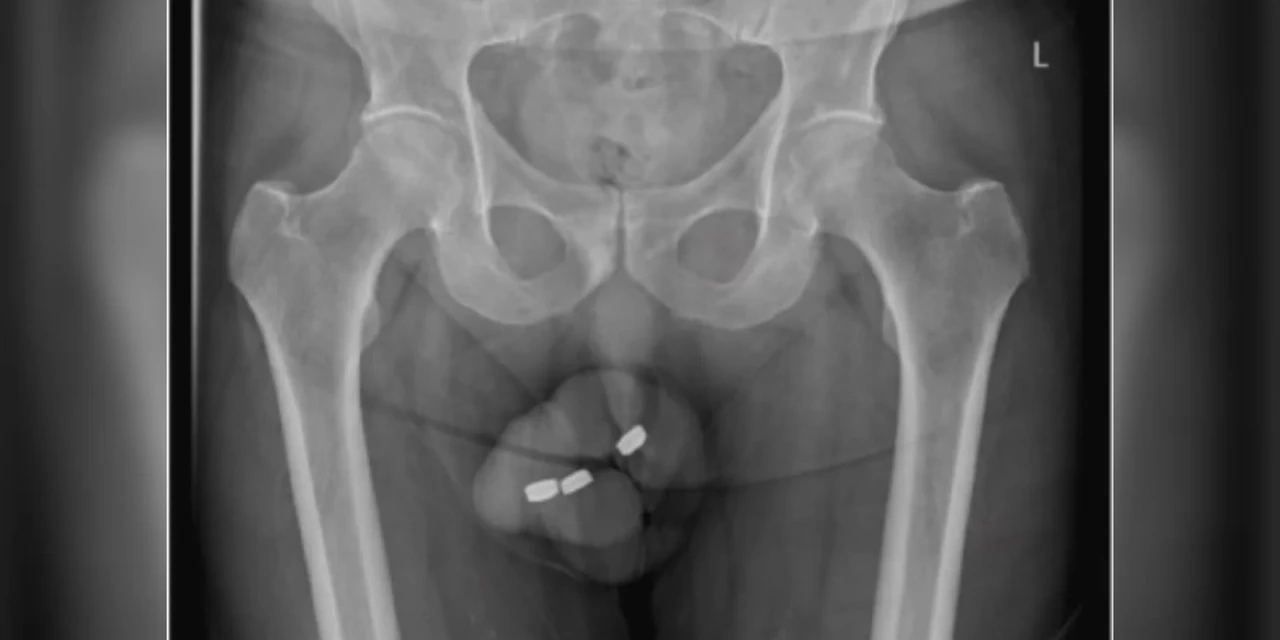

Idoso com impotência enfia baterias no pênis e perde parte do órgão

Um idoso procurou uma emergência médica na Austrália com fortes dores no pênis. O paciente, que não foi identificado por razões de privacidade, tinha enfiado três baterias semelhantes às balas tictac na uretra, canal do pênis por onde passa a urina. O idoso sofria com impotência sexual há três anos e já havia feito inclusive terapias de eletrochoque para recuperar suas ereções. O homem alegou que tinha o hábito de inserir corpos estranhos na uretra para se masturbar, mas neste caso as baterias entraram mais profundamente no órgão. Desesperado para retirá-las, ele acabou empurrando-as ainda mais profundamente. Ao chegar ao hospital, o paciente não conseguia urinar e estava com o órgão todo inchado. Além disso, a bateria enfiada por último havia se danificado lá dentro e os médicos temiam o vazamento de elementos corrosivos no corpo do paciente. “Este é o primeiro caso de inserção de baterias deste tipo na uretra. Sabemos de casos da inserção de uma grande variedade de corpos estranhos como fios, ossos, talheres, alfinetes, termômetros, cotonetes e vermes, mas bateira foi a primeira vez e os traumas de seus produtos químicos são extremamente prejudiciais”, escreveram os médicos em um artigo sobre o caso no na Urology Case Reports, publicado em 10/2. Homem passou por 2 cirurgias Os médicos que atenderam o paciente relataram ter tentado retirar as baterias com pinças, mas a dor impediu que o procedimento atingisse seu objetivo. O recurso seguinte foi sedar o idoso e retirar as baterias em uma operação cirúrgica. Durante a cirurgia, os médicos descobriram que a uretra do paciente estava queimada por conta do vazamento das substâncias corrosivas. Eles cuidaram das queimaduras, prescreveram antibióticos e deram alta para o homem após três dias. Dez dias depois, o homem retornou ao hospital com novo inchaço no pênis e muita secreção de pus acumulada no órgão, além de dificuldade de retração do prepúcio. Os médicos drenaram todo o líquido do pênis em uma nova cirurgia e descobriram que 8 cm da uretra havia necrosado, o que obrigou-os a retirar parte do órgão do paciente, com a substituição do canal por um catéter. O tecido ao redor foi raspado para evitar novas infecções.